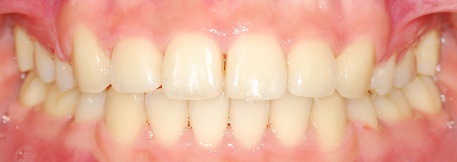

완성된 치아사진 보실게요ㅎㅎㅎ

정면 사진